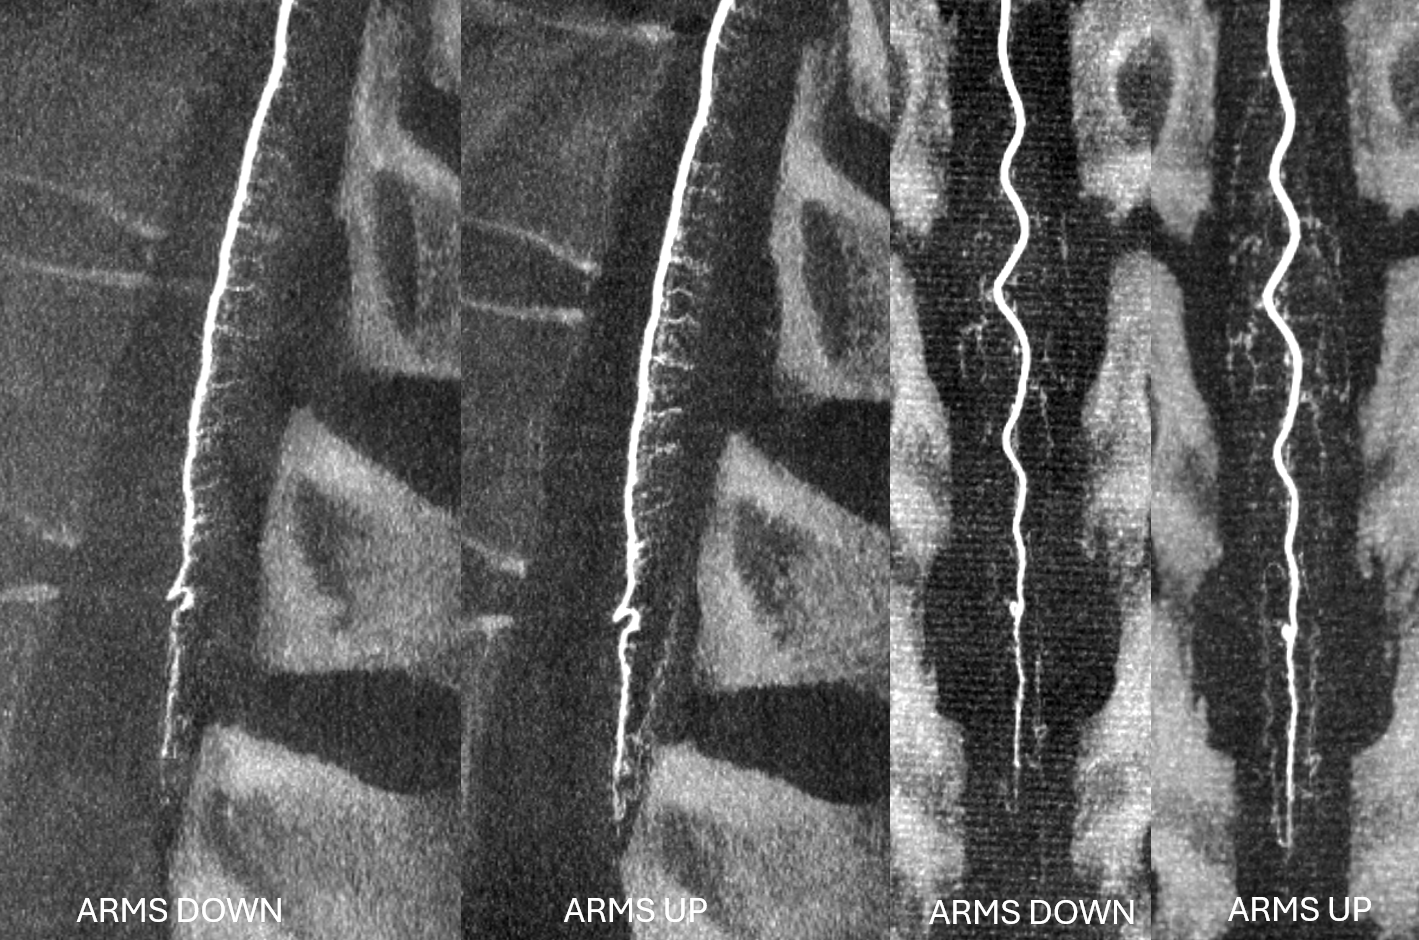

For thoracic and lumbar spine images, elevating arms above head makes a big difference. You have to be careful about brachial palsy with over-stretching, and making sure arms are secure. There is no free lunch — you want good results, you have to invest. GA, pharmacologic paralysis, breathold are all essential. Below are examples of the same patient — rotational angiography and reconstructed MIPs — arms down and arms up. The difference is obvious.

Arms down, arterial phase. Siemens Icono, 7 second micro dyna single volume, 1 cc/sec for 9 seconds, 2 second delay. The thickness is very heterogeneous — too thick with arms in lateral view (dark) and too thin in frontal view (light)

Arms UP, arterial phase. Siemens Icono, 7 second micro dyna single volume, 1 cc/sec for 9 seconds, 2 second delay.